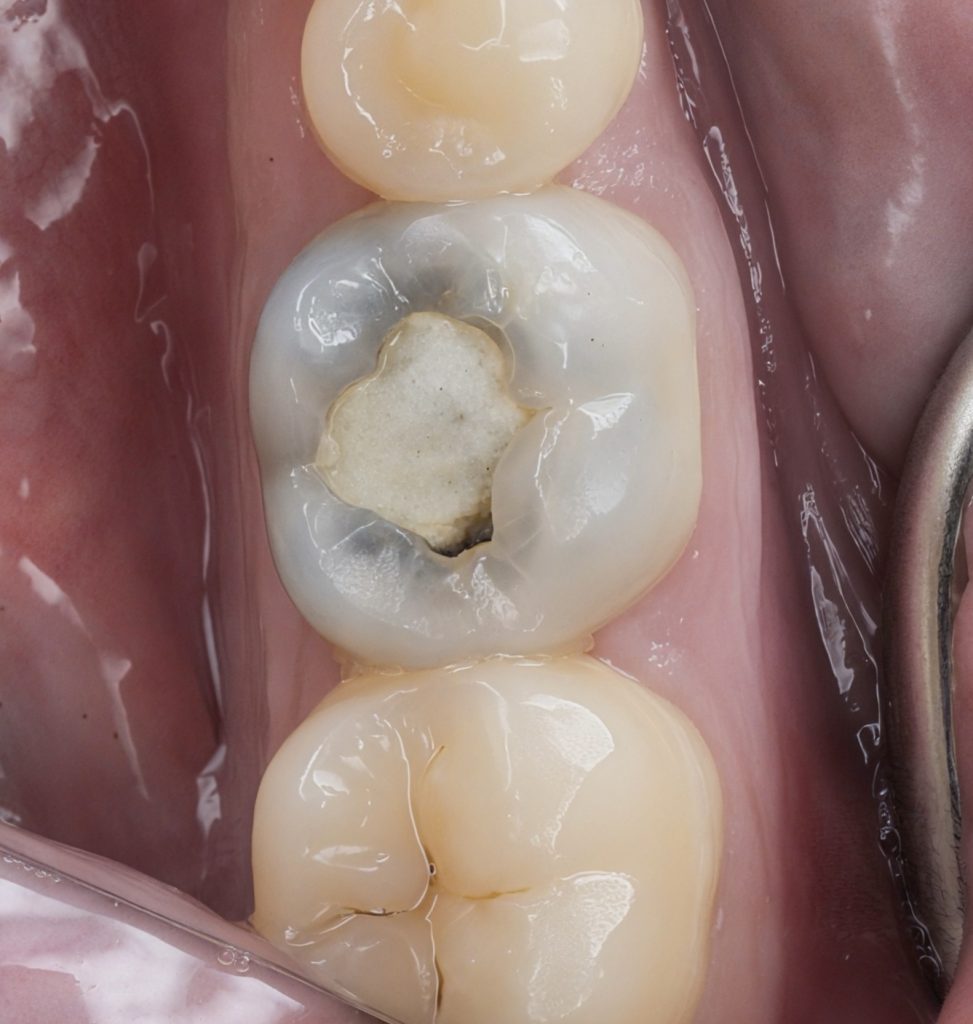

1. Isolation & Caries Removal

Rubber dam isolation was achieved to ensure absolute moisture control. Selective caries excavation was performed to remove infected dentin while conserving affected remineralizable dentin.

2. Conservative Endodontic Access

A contracted access cavity preserving pericervical dentin was created. Canal orifices were identified without unnecessary removal of dentin shelves, adhering to Ninja Access philosophy.

5. Biomimetic Core Build-Up & Cuspal Protection

To reinforce internal structure:

- Deep dentin sealed immediately post-endo with 4th generation adhesive (Total Etch)

- Dentin replacement performed using GC EverX Flow fiber-reinforced composite